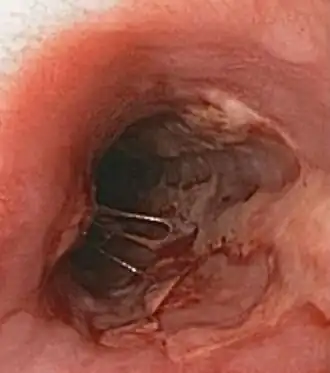

| Герпетический эзофагит | Герпетический эзофагит характеризуется болезненным или затруднённым глотанием. Часто протекает на фоне иммунодефицитов (например ВИЧ/СПИД) или в посттрансплантационном периоде. |